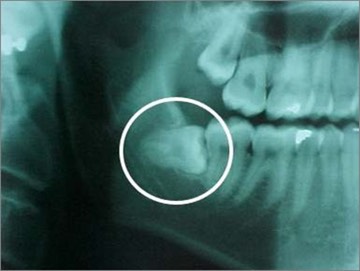

The basic problem is a lack of space. We have too many teeth to fit into our small jaws. Problematic wisdom teeth may emerge into the mouth but part of them remain covered under the gum or jaw bone.

A wisdom tooth is removed to correct an actual problem or to prevent future problems. When wisdom teeth come in, a number of problems can occur:

- Damage to other neighbouring teeth and bone.

- The development of a cyst.